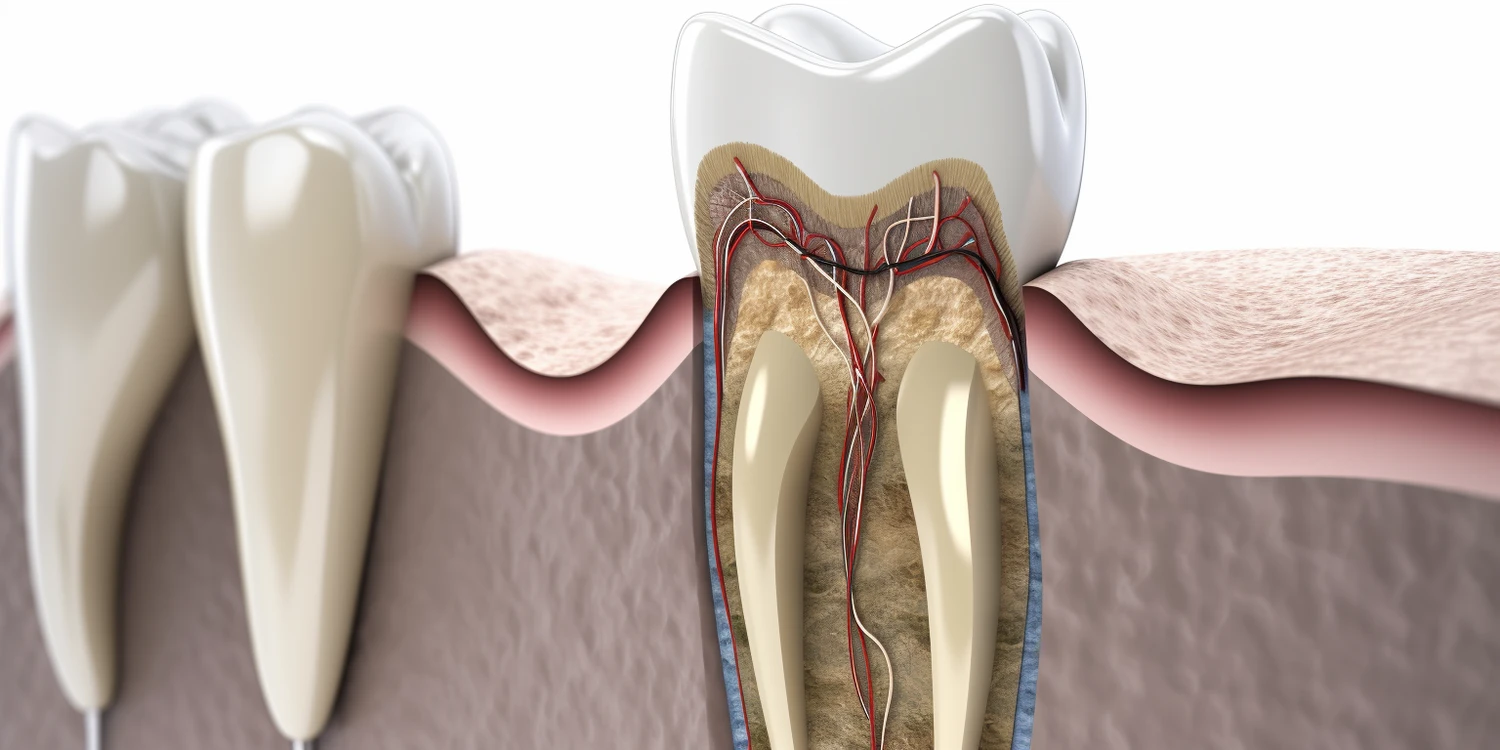

W Mińsku Mazowieckim, podobnie jak w innych miejscowościach, pacjenci borykają się z różnorodnymi problemami stomatologicznymi. Najczęściej występującymi schorzeniami są próchnica oraz choroby przyzębia, które mogą prowadzić do poważniejszych komplikacji zdrowotnych. Próchnica zębów jest wynikiem działania bakterii, które produkują kwasy niszczące szkliwo zębów. Regularne wizyty u stomatologa oraz odpowiednia higiena jamy ustnej mogą znacznie zmniejszyć ryzyko jej wystąpienia. Innym powszechnym problemem są bóle zębów spowodowane stanami zapalnymi lub urazami. W takich przypadkach niezbędna jest szybka interwencja specjalisty. Pacjenci często zgłaszają się również z problemami związanymi z estetyką uśmiechu, takimi jak przebarwienia czy nierównomierny kształt zębów.

W Mińsku Mazowieckim pacjenci mają dostęp do szerokiej gamy usług stomatologicznych, które odpowiadają na różnorodne potrzeby zdrowotne i estetyczne. Wśród podstawowych usług znajduje się profilaktyka, która obejmuje przeglądy stomatologiczne, fluoryzację oraz usuwanie kamienia nazębnego. Regularne czyszczenie zębów jest kluczowe dla zapobiegania próchnicy oraz chorobom dziąseł. Kolejną istotną kategorią usług są zabiegi związane z leczeniem próchnicy, które mogą obejmować wypełnienia kompozytowe, leczenie kanałowe oraz ekstrakcje zębów. Dla pacjentów pragnących poprawić estetykę swojego uśmiechu dostępne są zabiegi takie jak wybielanie zębów, licówki czy korony porcelanowe. W Mińsku Mazowieckim można również skorzystać z ortodoncji, która oferuje aparaty stałe i ruchome, a także nowoczesne metody leczenia, takie jak Invisalign. Dodatkowo, wielu stomatologów specjalizuje się w implantologii, co pozwala na odbudowę brakujących zębów za pomocą implantów dentystycznych.